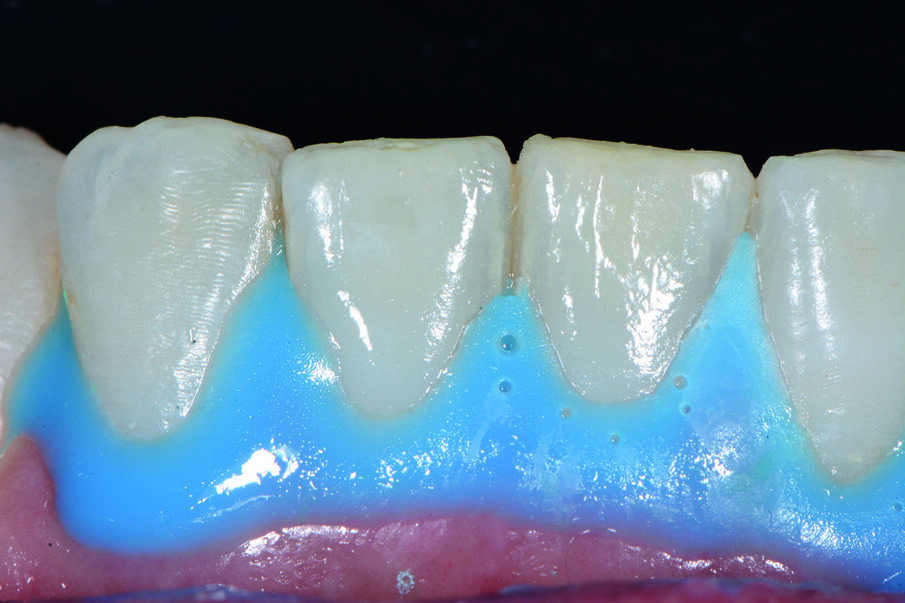

Prima del trattamento abbiamo applicato un rilevatore di placca alla fluoresceina Plac-o-Tect (Directa) per evidenziare la topografia della presenza di biofilm batterico nel cavo orale. Osserviamo la topografia del biofilm batterico presente e condividiamo con il paziente i siti più ritentivi di biofilm batterico in modo da avere una comunicazione non verbale del rivelatore, utile per il rinforzo motivazionale del paziente con l’obiettivo di migliorare l’efficacia dell’igiene orale domiciliare (Fig. 3).

La metodica D-BIOTECH è applicabile nella terapia parodontale non chirurgica, come approccio clinico meccanico o manuale nel deplaquing e nel debridment. Tale approccio permette di eseguire un lavoro minimamente invasivo poiché l’operatore può strumentare con polishing selettivo, airpolishing, ablatori o strumentazione manuale seguendo esclusivamente la topografia del biofilm batterico, poiché intercetta visivamente i siti più a rischio di infiammazione attraverso la colorazione del rivelatore.

La comunicazione non verbale visiva di questo approccio clinico nuovo permette un lavoro sicuramente più ergonomico per l’operatore, che sceglierà lo strumento o la tecnica operativa più performante per strumentare unicamente dove sono presenti biofilm batterico e discromie acquisite (Fig. 5).